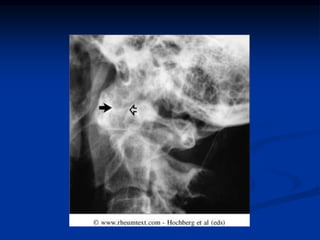

Radiographic Features

 Peri-articular osteopenia

 Uniform symmetric joint space narrowing

 Marginal subchondral erosions

 Joint Subluxations

 Joint destruction

 Collapse

 Ultrasound detects early soft tissue lesions.

 MRI has greatest sensitivity to detect

synovitis and marrow changes.